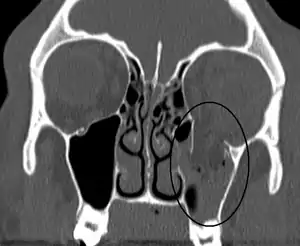

| An orbital blowout fracture of the floor of the left orbit. | |

Thin cut (2-3mm) CT scan with axial and coronal view is the optimal study of choice for orbital fractures.[8][11]

Plain radiographs, on the other hand, do not have the sensitively capture blowout fractures.[12] On Water's view radiograph, polypoid mass can be observed hanging from the floor into the maxillary antrum, classically known as teardrop sign, as it usually is in shape of a teardrop. This polypoid mass consists of herniated orbital contents, periorbital fat and inferior rectus muscle. The affected sinus is partially opacified on radiograph. Air-fluid level in maxillary sinus may sometimes be seen due to presence of blood. Lucency in orbits (on a radiograph) usually indicate orbital emphysema.